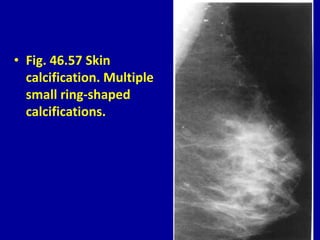

• Fig. 46.57 Skin

calcification. Multiple

small ring-shaped

calcifications.

• Fig. 46.57Skin calcification. Multiple small ring-shaped calcifications.